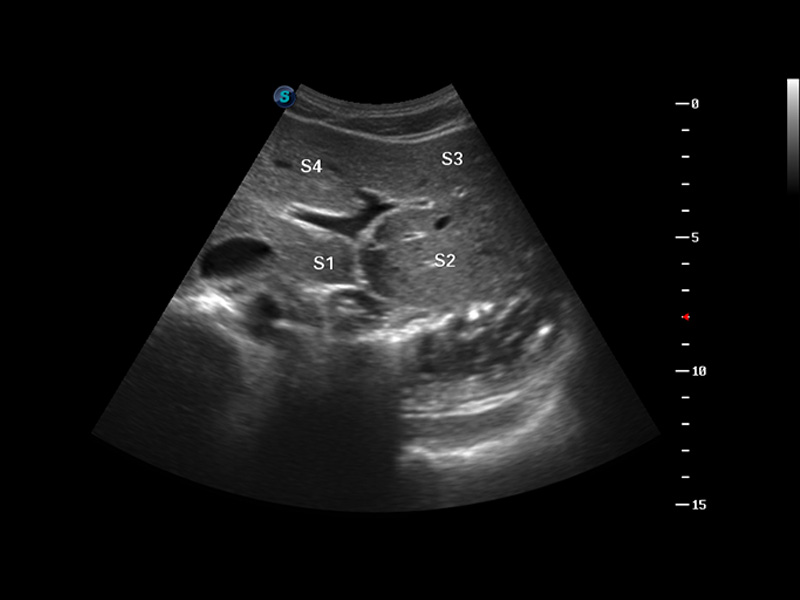

便携式彩色多普勒超声诊断仪

S8 EXP便携式彩色多普勒超声诊断仪是玖鼎集团研发的高端全身应用型便携彩超。高通道的VIS平台融合可视化(Visual)、智能化(Intelligent)和人性化(Smart)的特点,配以玖鼎集团自主研发生产的探头大家族,使您能够快速、准确的获得病人信息,提高工作效率的同时减轻疲劳。

3D/4D成像